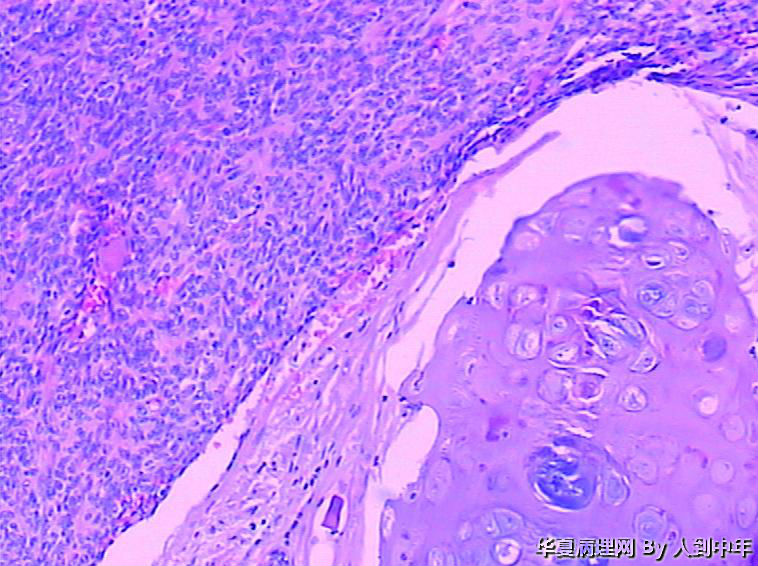

肺部肿瘤--类癌?求助大家

患者,男性,72岁,右肺中叶占位,肺门部肿物,散在多结节状,直径0.2-2.2cm。

没见过,我们也没有免疫组化,全靠HE。临床就想诊断了肿瘤让患者出院,我还想让患者去肿瘤会诊?大家怎么诊断?遇到临床不想会诊这种情况又如何办?

标签:肺部肿瘤 中央型 类癌 会诊

癌,微囊、细胞梭形或立方、癌巢周边细胞见栅栏状,不能排除基底细胞样癌。多结节,也要排除转移性涎腺型恶性肿瘤,腺样囊腺癌等。

微囊、细胞梭形或立方、癌巢周边细胞见栅栏状,不能排除基底细胞样癌。

微囊、细胞梭形或立方、癌巢周边细胞见栅栏状(图22),不能排除基底细胞样癌。

低分化癌,可能伴神经内分泌分化。不能标记也要建议会诊,去不去是他们的事

低分化癌,看到有腺样结构,肿瘤多结节,也要排除转移。

NT。需计数分裂像分级。